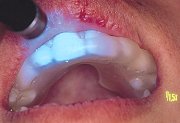

完成したスプリント。下顎安静位からの閉口位で を咬合接触させた。偏心運動は でガイドさせた。 |